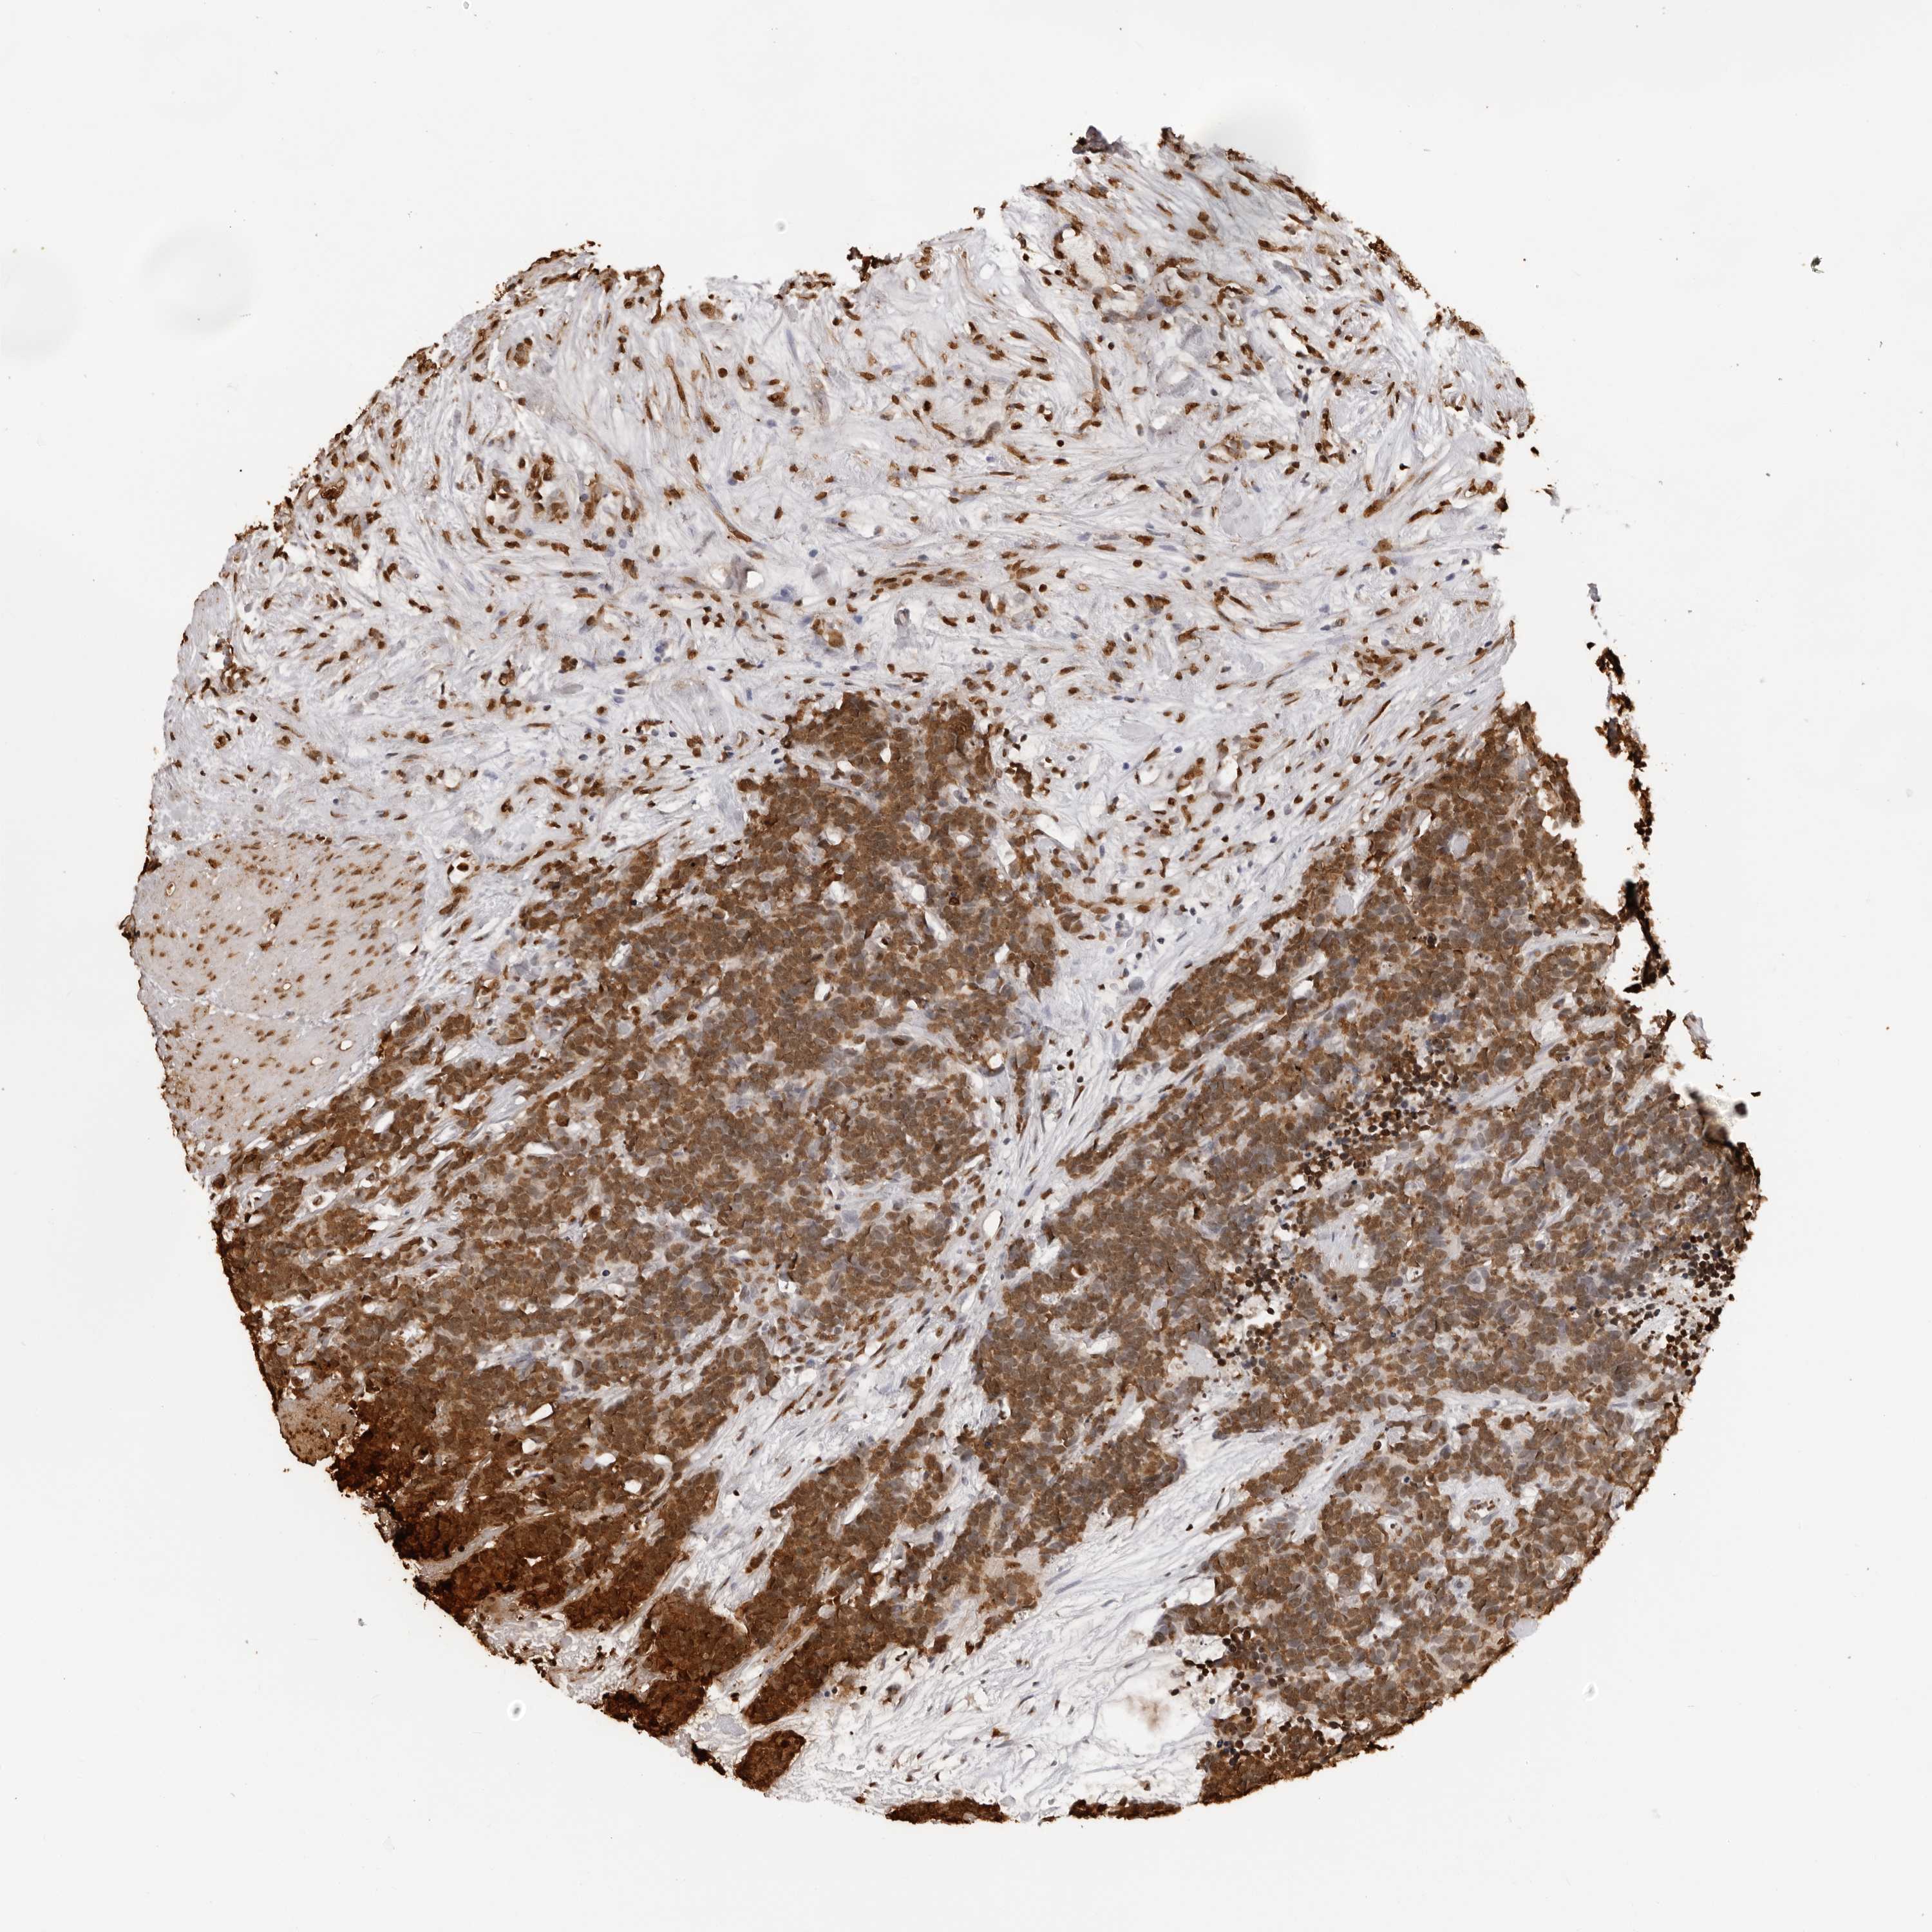

CARCINOID - Protein expressioni

A mouse-over function shows sample information and annotation data. Click on an image to view it in a full screen mode. Samples can be filtered based on level of antibody staining by selecting one or several of the following categories: high, medium, low and not detected. The assay and annotation is described here.

Each image is clickable and will lead to virtual microscopy that enables deeper exploration of all samples and also displays staining intensity scores, fraction scores and subcellular localization as well as patient and tissue information for each sample.

Antibody HPA024037

Staining

High

Intensity

Strong

Quantity

>75%

Location

Nuclear

Carcinoid, malignant, NOS